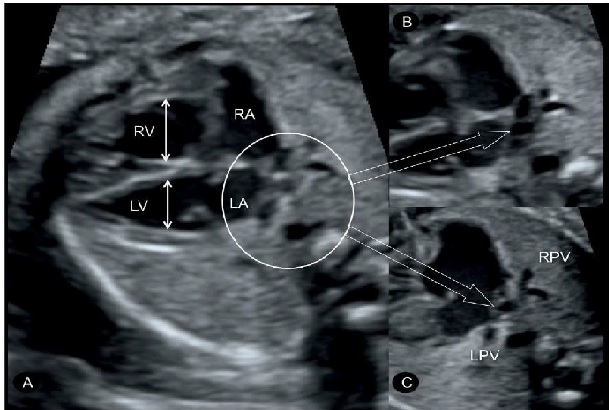

Hình 2: Mặt cắt ngang 4 buồng tim: Hình ảnh bất thường hồi lưu tĩnh mạch phổi toàn phần (TAPVR) thể trên tim (type I: supracardiac). Hình phóng to phía sau tâm nhĩ trái B và C. Lưu ý tâm thất phải (RV) và nhĩ phải (RA) lớn hơn tâm nhĩ trái (LV) và thất trái (LA) do tĩnh mạch phổi gián tiếp đổ vào nhĩ phải. Cả hai tĩnh mạch phổi phải (RPV) và tĩnh mạch phổi trái (LPV) đều không đổ vào nhĩ trái mà đổ vào tĩnh mạch hội lưu (confluent vein) “mũi tên rỗng”.